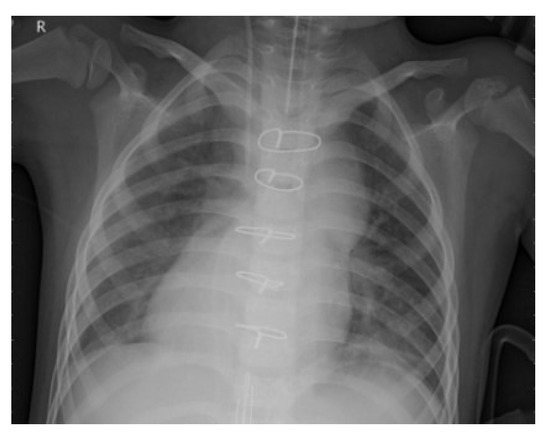

Enhanced ResNet-50 with Multi-Feature Fusion for Robust Detection of Pneumonia in Chest X-Ray Images

by Neenu Sebastian and B. Ankayarkanni

Diagnostics 2025, 15(16), 2041; https://doi.org/10.3390/diagnostics15162041 - 14 Aug 2025

Background/Objectives: Pneumonia is a critical lung infection that demands timely and precise diagnosis, particularly during the evaluation of chest X-ray images. Deep learning is widely used for pneumonia detection but faces challenges such as poor denoising, limited feature diversity, low interpretability, and class [...] Read more.

Background/Objectives: Pneumonia is a critical lung infection that demands timely and precise diagnosis, particularly during the evaluation of chest X-ray images. Deep learning is widely used for pneumonia detection but faces challenges such as poor denoising, limited feature diversity, low interpretability, and class imbalance issues. This study aims to develop an optimized ResNet-50 based framework for accurate pneumonia detection. Methods: The proposed approach integrates Multiscale Curvelet Filtering with Directional Denoising (MCF-DD) as a preprocessing step to suppress noise while preserving diagnostic details. Multi-feature fusion is performed by combining deep features extracted from ResNet-50 with handcrafted texture descriptors such as Local Binary Patterns (LBPs), leveraging both semantic and structural information. Precision attention mechanisms are incorporated to enhance interpretability by highlighting diagnostically relevant regions. Results: Validation on the Kaggle chest radiograph dataset demonstrates that the proposed model achieves higher accuracy, sensitivity, specificity, and other performance metrics compared to existing methods. The inclusion of MCF-DD preprocessing, multi-feature fusion, and precision attention contributes to improved robustness and diagnostic reliability. Conclusions: The optimized ResNet-50 framework, enhanced by noise suppression, multi-feature fusion, and attention mechanisms, offers a more accurate and interpretable solution for pneumonia detection from chest X-ray images, addressing key challenges in existing deep learning approaches. Full article